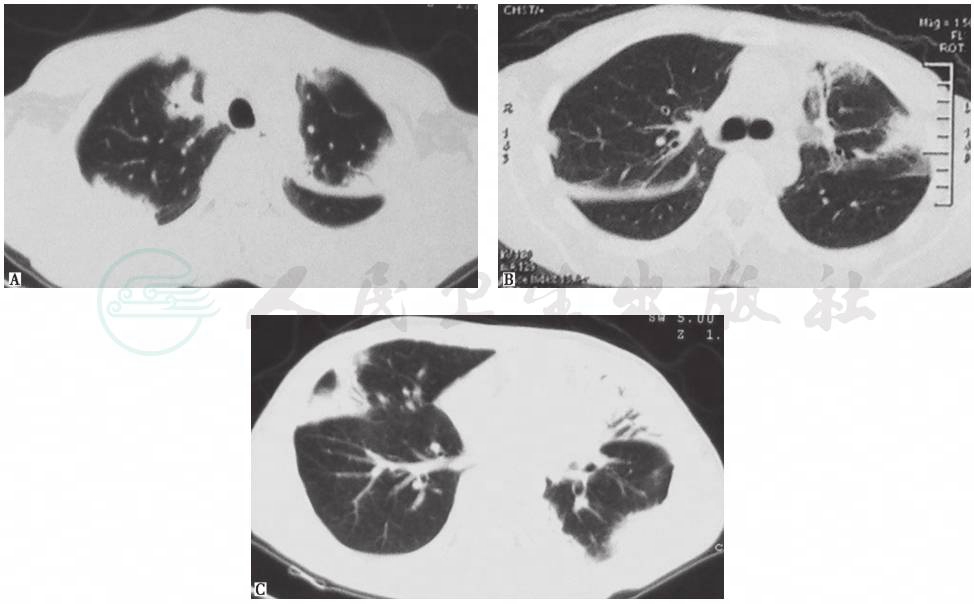

随访结果:醋酸泼尼松40mg(每天1次)并予护胃、补钙等治疗3天后,患者干咳症状明显好转,未诉其他不适。继续口服激素治疗2个月后复查胸部CT,显示病变明显好转(图4)。

图4 激素治疗后胸部影像学变化

A~C.2013年1月30日(泼尼松40mg治疗2周后)胸部CT显示肺部病变较前明显好转;D~F.2013年2月20日(泼尼松治疗6周后)胸部CT提示肺部病变较前进一步好转